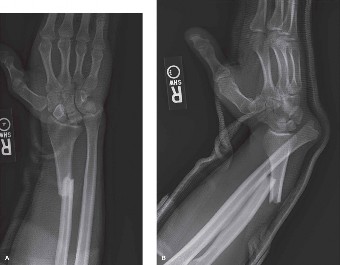

A 34-year-old, right-hand-dominant male is brought to the emergency department by his friends with a chief co…